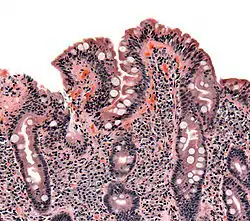

![]() صورة لخزعة نسيجية تظهر أعراض داء بطني على الأمعاء صورة لخزعة نسيجية تظهر أعراض داء بطني على الأمعاء | |